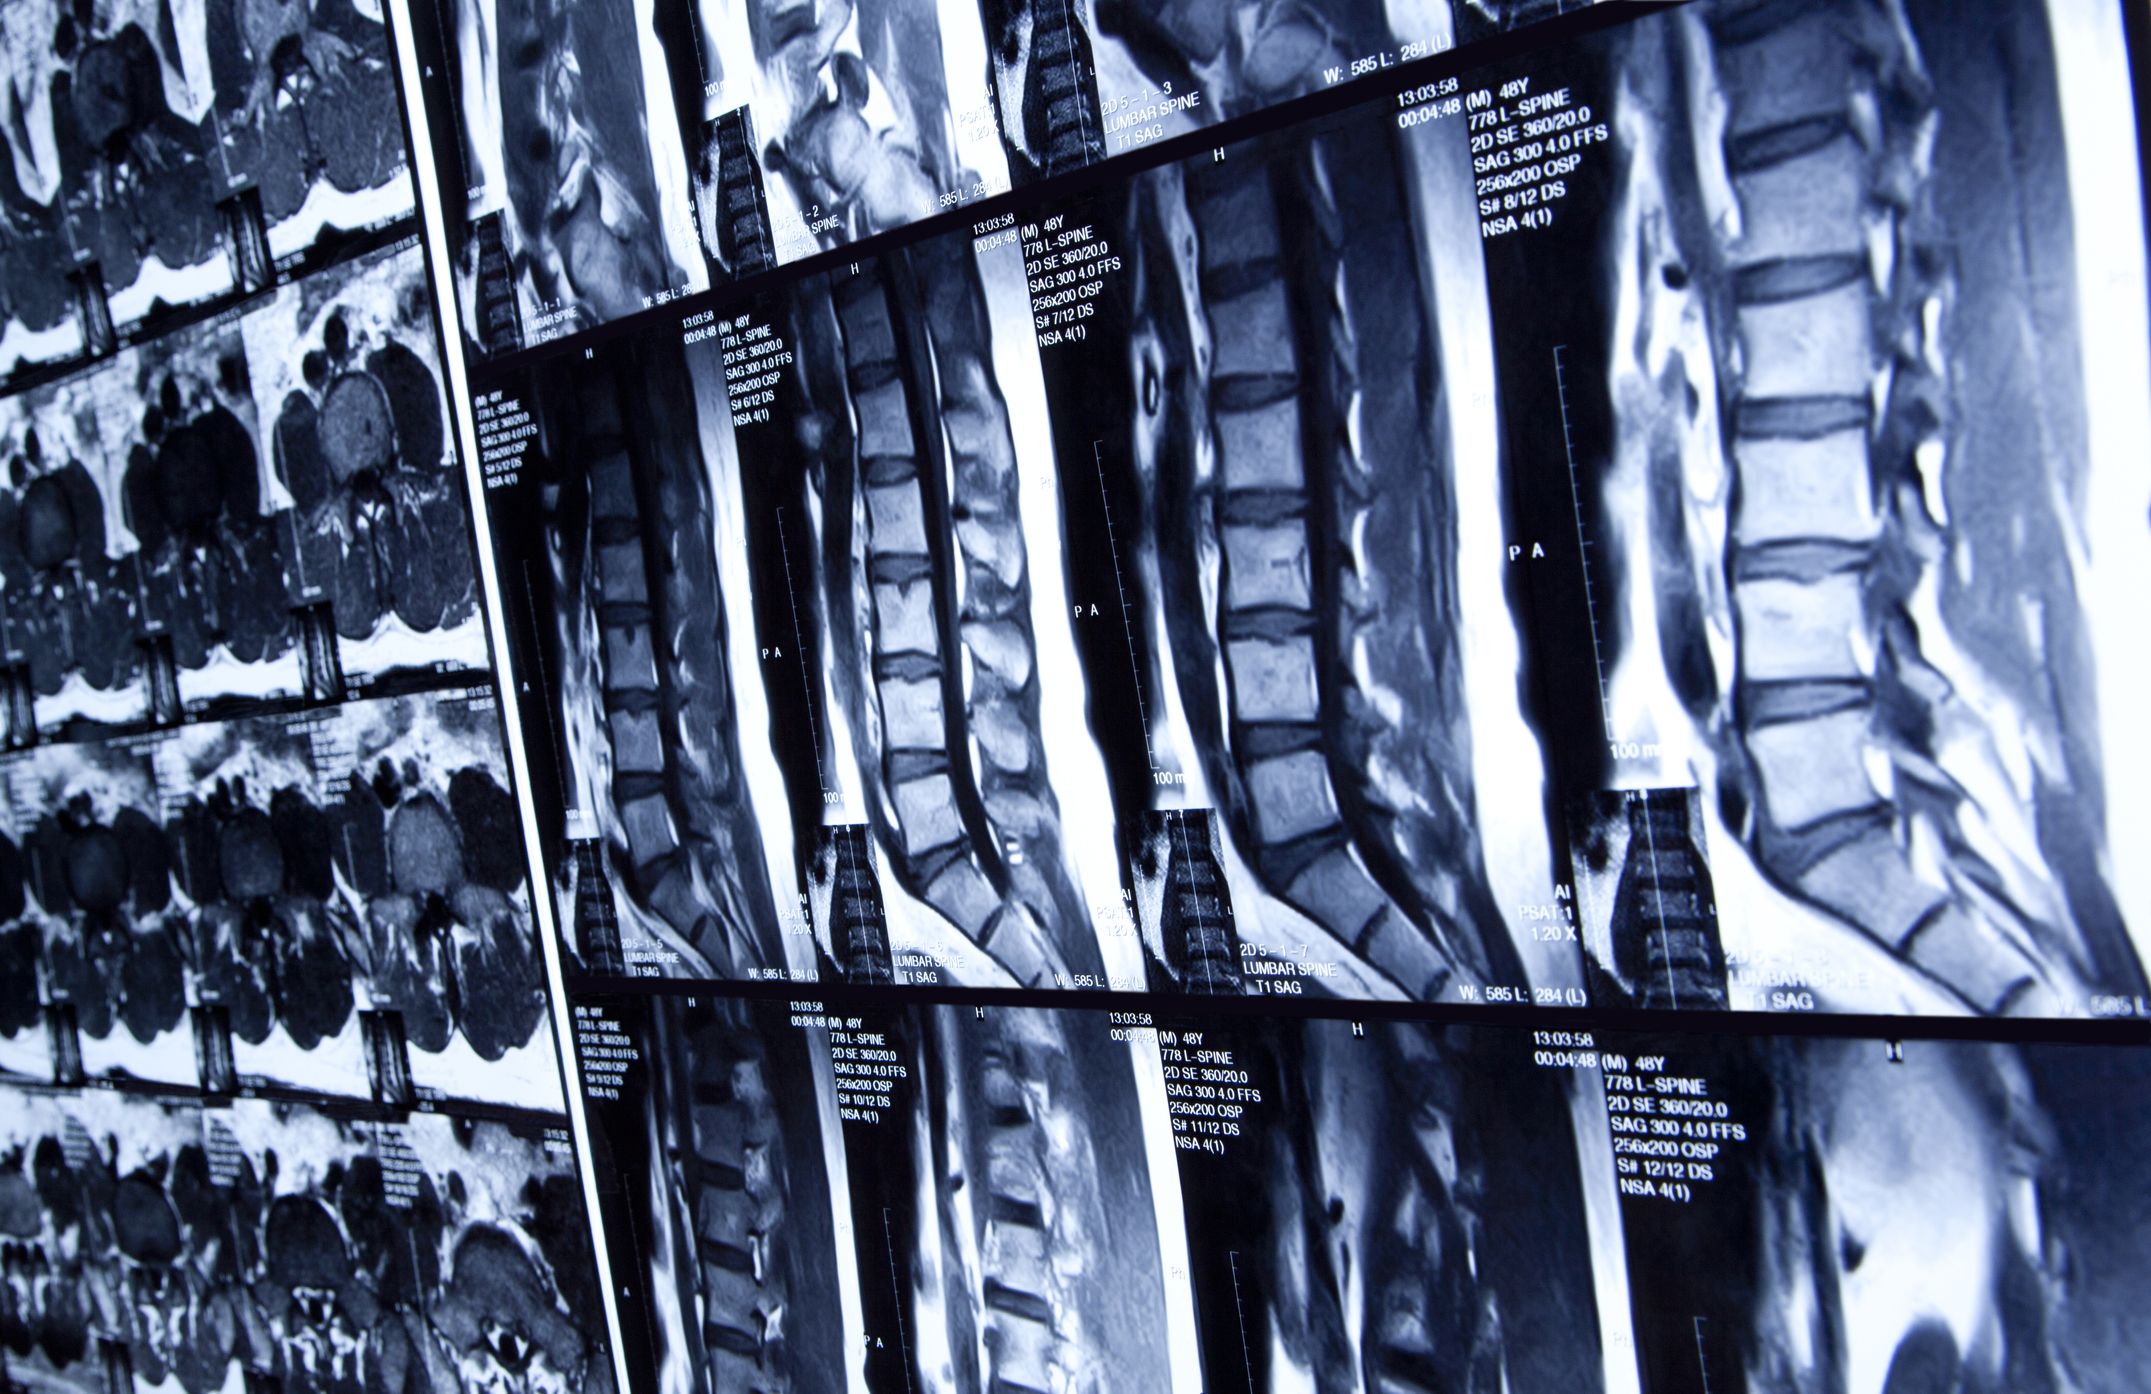

spinal cord x ray